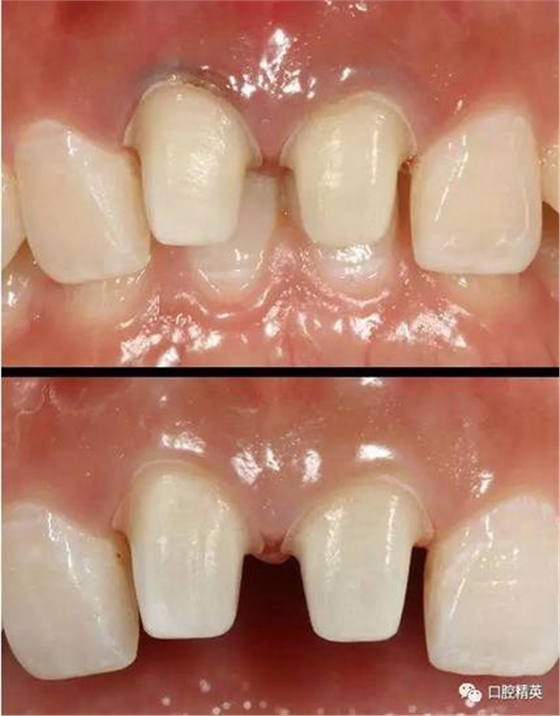

可見(jiàn)兩側(cè)齦緣外形不平整

激光休整牙齦前后

臨時(shí)冠修復(fù)

使用原始模翻制的臨時(shí)冠

術(shù)前,術(shù)中,術(shù)后對(duì)比

對(duì)比來(lái)看基本達(dá)到患者預(yù)期

有一點(diǎn)不足之處在于齦緣的高低不完全一致,補(bǔ)救辦法同上——激光輕掃